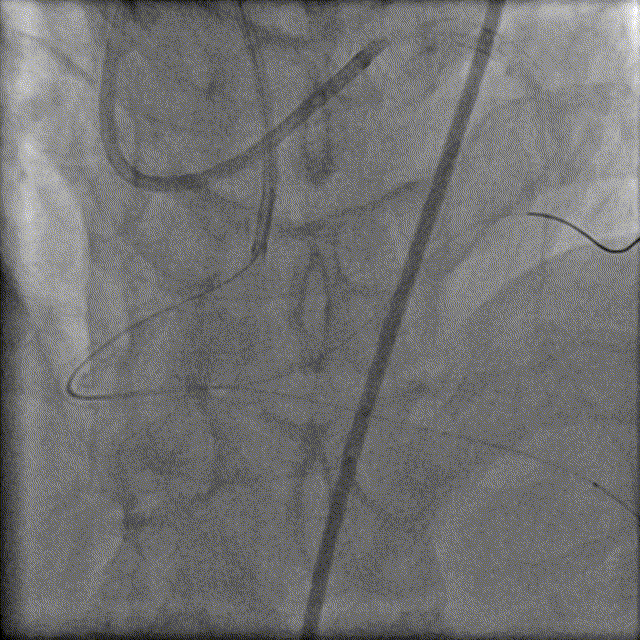

冠脉造影

LM未见异常,LAD原支架内血流通畅,支架近端可见局限性偏心狭窄90%,中远段未见狭窄或闭塞,前向血流TIMI-3级;中间支近中段弥漫性狭窄50%-60%。

LCX近段、中段、远段及分支均未见狭窄或闭塞,前向血流TIMI-3级。

RCA原支架内100%闭塞,前向血流TIMI-0级;可见LAD向RCA发出侧支,侧支血流1级。